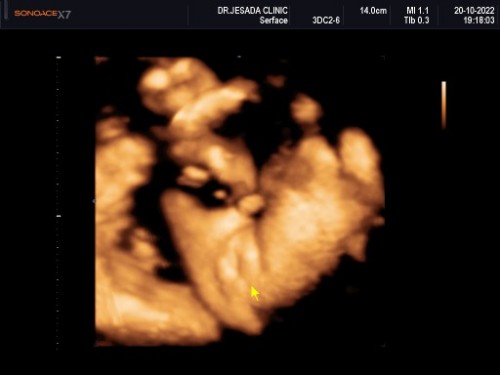

เพศน้องแบบนี้100%แล้วใช่ไหมคะแม่

29วีค น้ำหนักน้อง1280g

เพศหญิงใช่ไหมคะ

ชัดมากคะแม่

ไม่น่าเปลี่ยนแล้วนะคะแม่ เพราะยังไงเพศก็ถูกกำหนดตั้งแต่การปฏิสนธิแล้ว